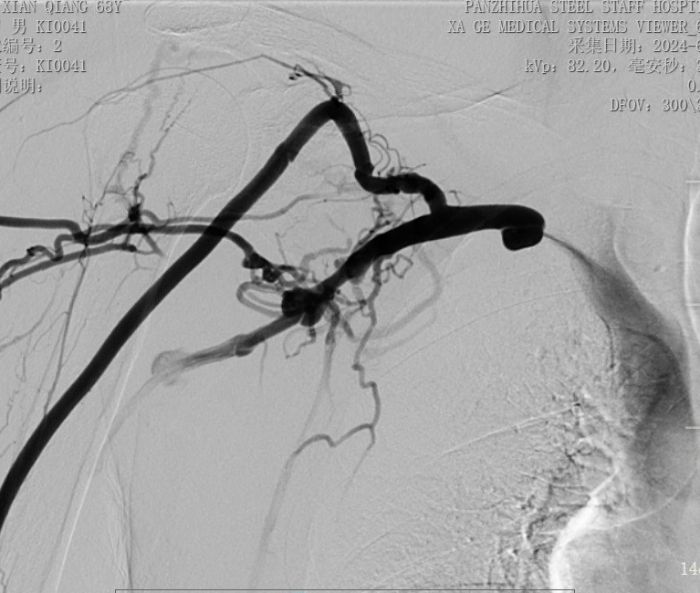

術前造影顯示右鎖骨下靜脈幾乎閉塞

手術中,主刀醫(yī)生唐靜通過DSA順利對人工血管中形成的血栓進行了取栓。之后,在中心靜脈造影下,發(fā)現(xiàn)患者中心靜脈外周有2cm的狹窄,尤其是右鎖骨下靜脈得狹窄已經嚴重到幾乎閉塞,針眼大小的縫隙僅能容下導絲通過。經過反復嘗試與不懈努力,終于將導絲置入,并用12 *40mm的球囊擴張,右鎖骨下靜脈成功開通,患者透析的通道打開了。術后,家屬看著消腫的手臂感激萬分,眼淚奪眶而出。